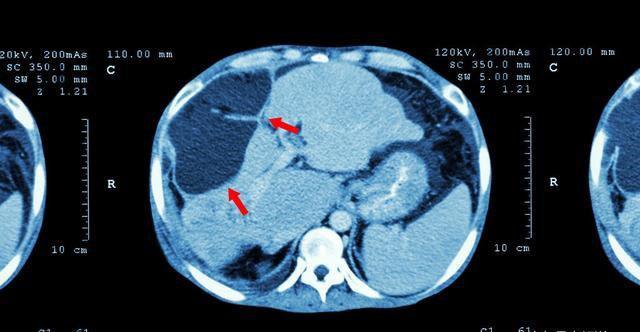

3.上腹部CT CT的分辨率远远高于超声,图像清晰而稳定,能全面客观地反映肝癌的特性,可用于肝癌常规诊断检查。CT增强扫描可清楚地显示肝癌的大小、数目、形态、部位、边界、肿瘤血供丰富程度,以及与肝内管道的关系。CT动态增强扫描可以显著提高小肝癌的检出率。

CT scan of upper abdomen : show abnormal mass at?